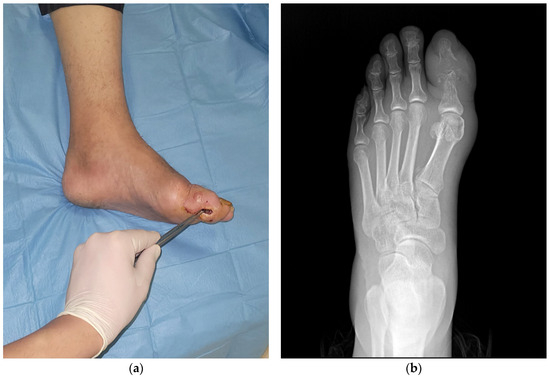

Orthopedic Imaging and Diagnostics: Cutting-edge imaging techniques, such as MRI, CT, ultrasound, electrophysiological studies and nuclear medicine, to diagnose and monitor musculoskeletal conditions.